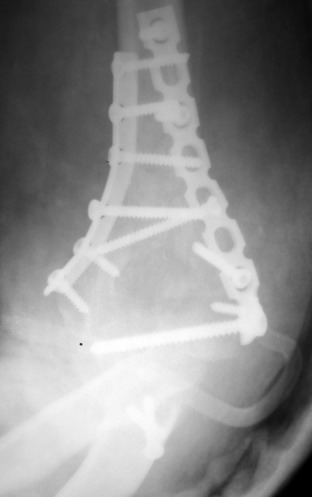

Солидарен с мнением обоих Александров (Челнокова и Рыкова): точную репозицию такого перелома вряд ли удастся выполнить закрыто. Даже во время открытого вмешательства это сделать непросто. Неслучайно предложен костно-пластический доступ с временным отсечением локтевого отростка. И по методу фиксации согласен с Александром Челноковым: 2 пластины. В качестве примера привожу рентгенограммы одного из наших пациентов с аналогичным повреждением.